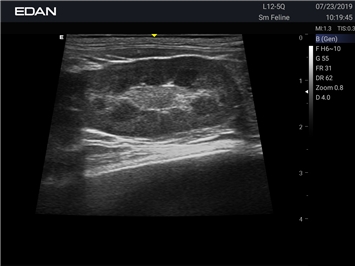

УЗИ-аппарат

EDAN Acclarix AX2 VET

Ветеринарный ультразвук одним нажатием. Система Acclarix AX2 VET разработана с целью обеспечить бескомпромиссную производительность по доступной цене. Наличие уникальных двойных аккумуляторов в легком корпусе массой 4,5 кг из магниевого сплава позволяет системе Acclarix AX2 VET удовлетворять все потребности ветеринарных исследований, сохранив низкую стоимость.

EDAN Acclarix AX2 VET представляет собой специализированную ветеринарную ультразвуковую систему, сочетающую высокую производительность с доступной ценой. Благодаря продуманной конструкции и передовым технологиям, система обеспечивает качественную диагностику животных различных видов.